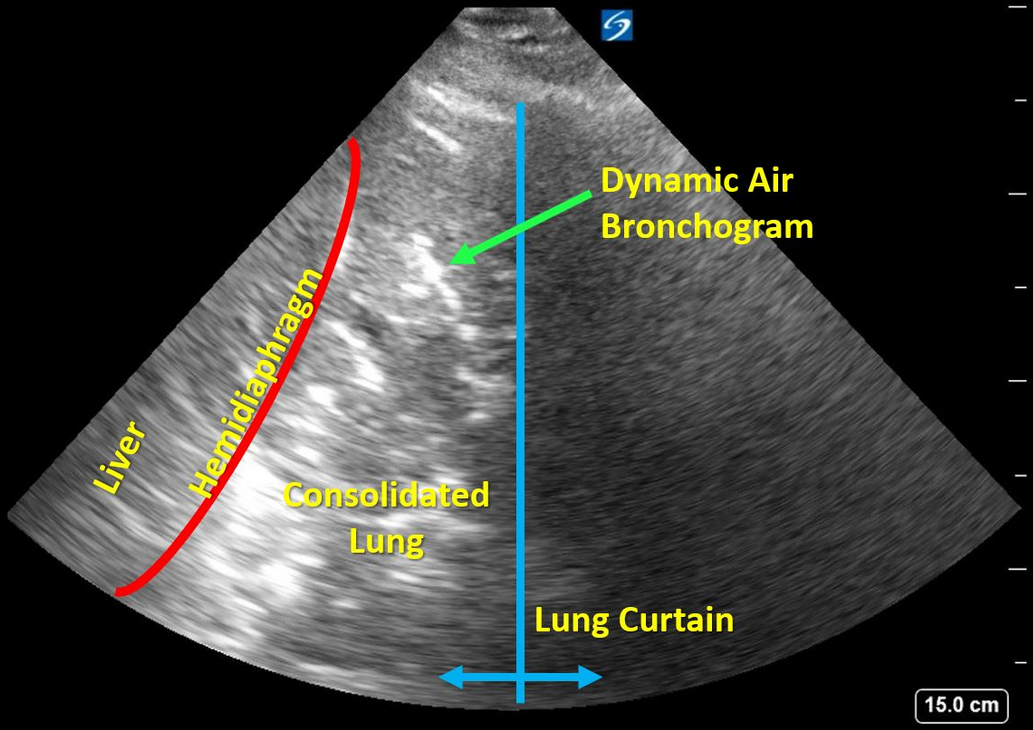

The history in this stem is that of a man who has risk factors for each of the four diagnoses offered: lung cancer, pneumonia, empyema, and pneumothorax. The learner is offered an ultrasonographic video of the right base from which to narrow down the differential diagnosis. A frame shot of the video is shown in Figure 1 and is labeled for the learner’s convenience. Please refer to the video, as the key findings require motion. A lung curtain from the still aerated right upper lobe can be seen moving back and forth from the right side of the video. There is “sonographic hepatization” of the right lower lobe, a term used to describe dense consolidation where the airless lung takes on the ultrasonographic appearance of liver. The short, segmented, echogenic structures within the area of consolidated lung are bronchi that contain minute amounts of air, rendering them hyperechoic. In the video, one or two of these bronchi contain small bubbles of air that are moving back and forth with tidal respiration. These are termed “dynamic air bronchograms.” Lichtenstein and colleagues studied 52 patients with proven bacterial pneumonia and 16 patients with resorptive atelectasis typical of patients with airway occlusion from a tumor. The presence of dynamic air bronchograms had a specificity of 94% and a positive predictive value of 97% for the diagnosis of pneumonia. In other words, the presence of dynamic air bronchograms in this patient is most likely to represent pneumonia rather than atelectasis from central airway obstruction. The sensitivity and negative predictive value of dynamic air bronchograms were lower (61% and 43%, respectively). Thus, the absence of this finding does not exclude a diagnosis of pneumonia.

Empyema in this location might look very complex and echogenic, but it would not demonstrate the characteristic short hyperechoic static and dynamic air bronchograms. If pneumothorax had been present, the interface between the chest wall and the pneumothorax would generate bold A-line artifacts resembling normal lung minus lung sliding.1234